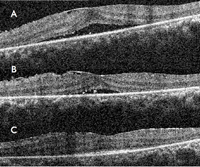

En la imagen superior de la

Figura 1 puede verse una OCT macular realizada con HD- OCT (Cirrus de Zeiss) aumentada, y en la imagen inferior realizada con OCT de última generación DRI-OCT (Atlantis de Topcon).

Figura 1. OCT en voluntarios sanos. Imagen superior: OCT realizada con HD-OCT (Cirrus de Zeiss); imagen inferior: OCT realizada con tecnología DRI-OCT (Atlantis de Topcon). En ambas imágenes pueden distinguirse las cuatro líneas hiperreflectivas de la retina externa (desde la parte vítrea o más interna a la parte coroidea o más externa): membrana limitante externa (MLE), zona de los elipsoides (EZ), zona de interdigitación (IZ) y complejo EPR-membrana de Bruch.